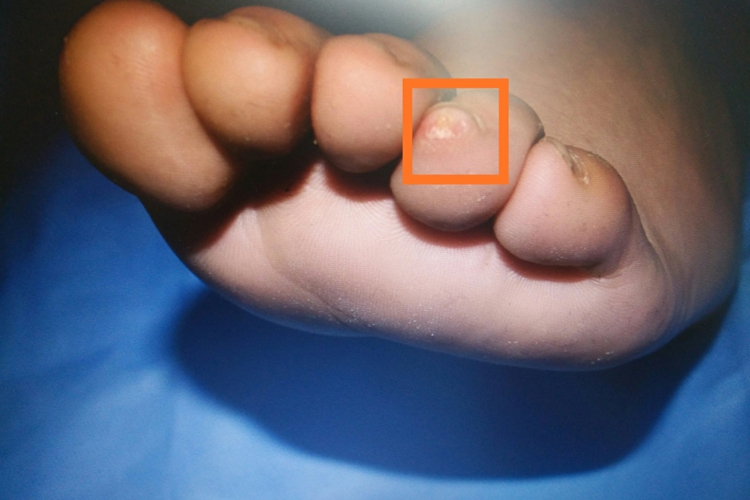

甲下骨疣表现为疼痛、肿胀,局部可见破溃和感染,病变部位多位于指端末节。X线上可以看到脚趾周围的硬的骨性包块,部分病变边界清楚,但更多表现为边界不清,与深层的骨相连或不相连。